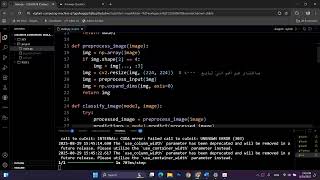

MRI Tumor Detection by Néstor Gómez Artiles

AI-driven brain tumor detection from MRI scans with real-time web predictions.